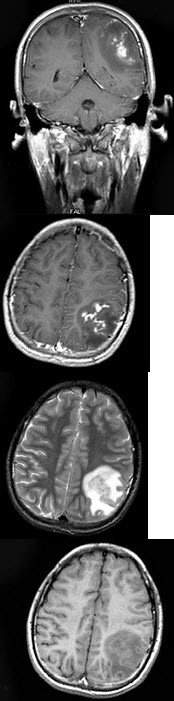

男,15岁。头痛呕吐数天。生活在疫区。MRI检查如图示。最可能的诊断是( )

A:脑血吸虫病

B:脑脓肿

C:脑内结核瘤

D:胶质瘤

E:未见异常